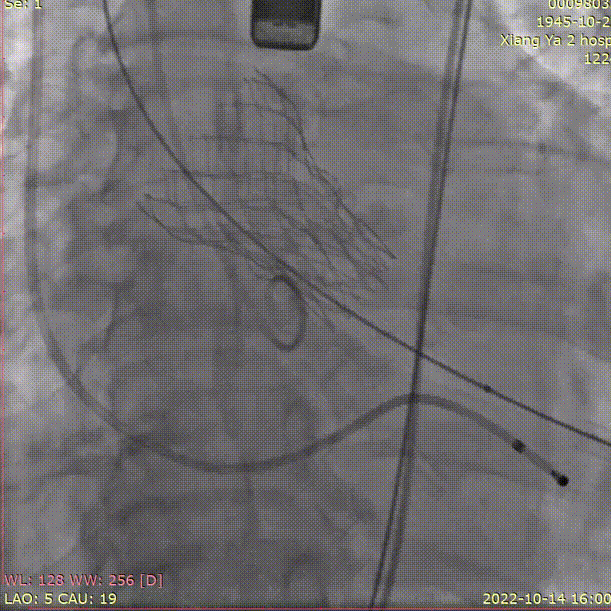

手术关键步骤

A.主动脉根部造影

B. 不前扩,输送系统一步到位

C. 应用交界贴合技术调整人工瓣膜,到安全梢固定位置,定位好,不需要回收,直接释放

D. 瓣膜释放后造影

E.球囊后扩

F. 最终造影